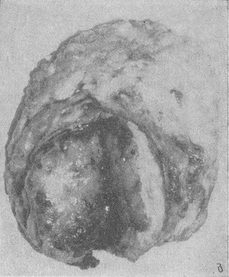

Филлоидная фіброаденома. Морфологічно филлоидная фіброаденома являє собою сполучнотканинну багатоклітинну пухлина з безліччю порожнин і характерним «листовидным» розташуванням клітинних полів (рис. 2). Морфологічна інтерпретація її складна через безліч перехідних типів і ступенів зрілості. Пухлина розглядається як найважливіша ланка в ланцюзі фіброаденоматоз - фіброаденома - филлоидная пухлина - саркома (Фікс А. Ф., 1969).

Клінічно у більшості пухлини мають чіткі межі, гладку або поліциклічну поверхню, тугоеластіческой або неоднорідну консистенцію, при якій ділянки удаваного розм'якшення і флуктуації чергуються з більш щільними. Розміри листоподібних пухлин можуть варіювати від невеликих до гігантських. Характерні тривалість існування пухлини в молочній залозі (у 56 наших хворих пухлина виявлена в строки від 1 року до 30 років, в середньому за 180 міс до обігу) і швидке зростання або прискорення його в останні місяці перед операцією (56,8%). Середній вік хворих 41,2 року (від 15 до 67 років), причому малигнизированные форми (у одній з 10 таких хворих) спостерігалися у старших вікових групах (35-65 років).